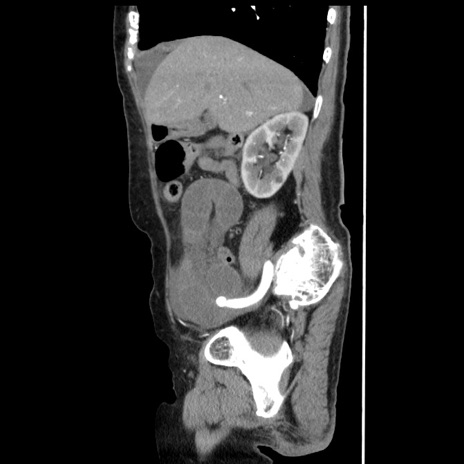

冠状断像

【症例】80歳代女性

【主訴】腹痛

【現病歴】8時間前から腹痛あり来院。

【既往歴】糖尿病、脂質異常症、子宮体癌にて子宮全摘術

【身体所見】意識清明・会話良好だが腹痛で苦悶様、全腹部にわたって反跳痛と圧痛あり

【データ】WBC 13600、CRP 0.14、LDH 224、CK 90